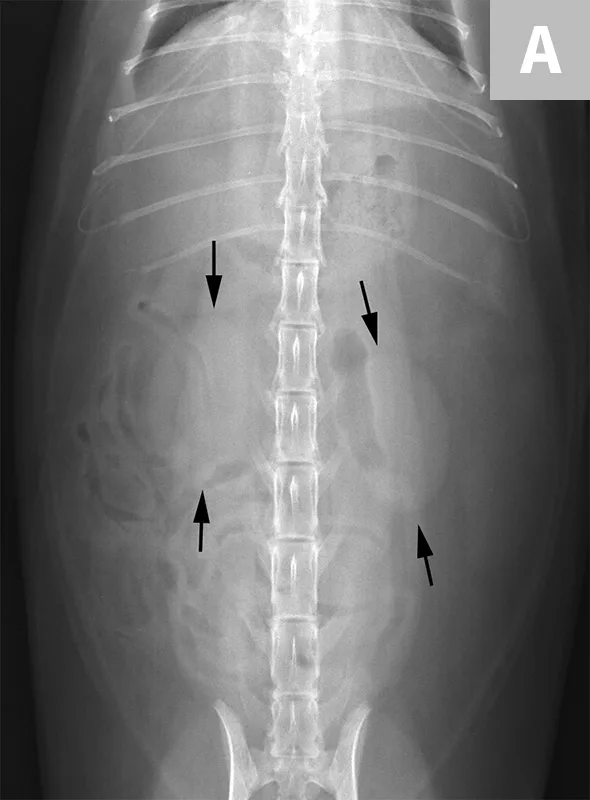

FIGURE 1A

Ventrodorsal radiograph of a normal cat for evaluation of the kidneys (arrows). Note the bean-shaped appearance, smooth capsular margin, normal size (approximately 2.2× the length of L2) and location. Both kidneys are more readily seen in this cat due to the amount of retroperitoneal fat. In the dog, the left kidney is easier to identify and evaluate routinely than the right, as the cranial pole of the right kidney border effaces with the renal fossa of the caudate lobe of the liver.